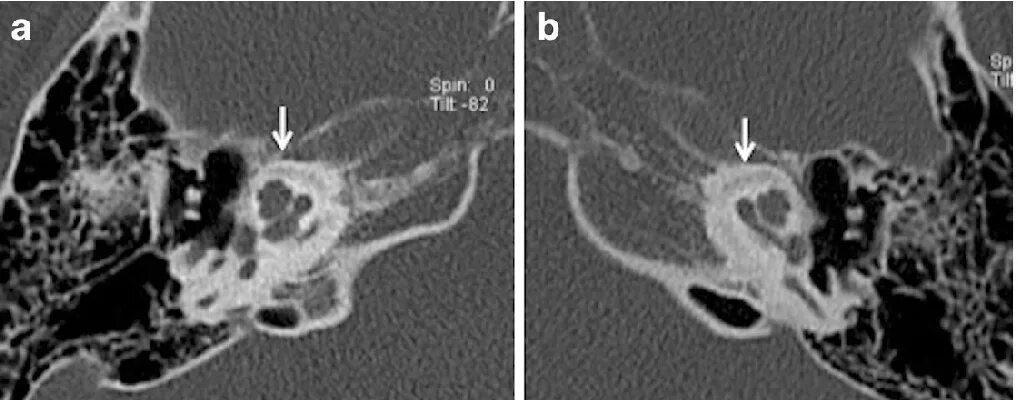

Кохлеарный отосклероз